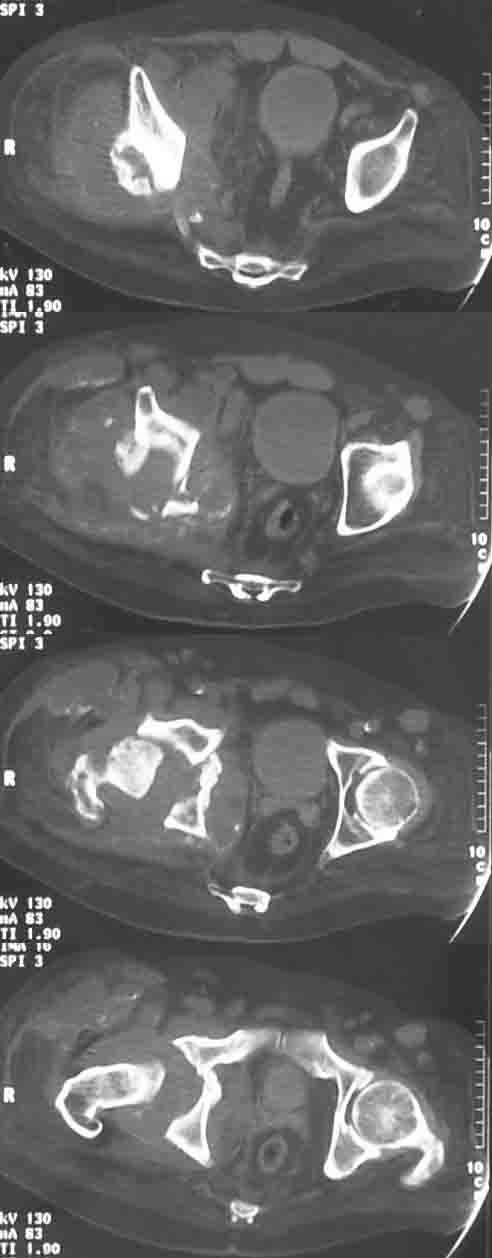

Дрогие коллеги,Обратился пациент, М-44, с опухолью правой тазовой кости, однако не все пока укладывается в обычное течение:

относительно медленный рост, нет интоксикации, нет снижения веса, нет метастазов, очень плотная ткань, при гистологическом исследовании после широкой открытой биопсии видны лишь элементы воспаления, фиброз, хрящевые включения. Рана зажила первично. В анамнезе тромбоцитемия, оперирована грыжа Шморля, практически нижний парапарез.

Может есть какое-то специфичекое поражение костей, когда такая рентгенологические проявления?С уважением, И.И.

Приложите, пожалуйста, рентгенограму таза в добавок к КТ. Скорее всего вы имеете дела с инфекцией тазобедренного сустава и последствующим остеомиелитом. Повторите биопсию и пошлите ткань и внутресуставную жидкость на бактериальный анализ, включая туберкулёз.

Сустав Шарко--другой вариант. Особено у пациента у которого парапарез. У него сильные боли от этой "опухоли?" Сделайте анализы ESR, CRP(извините, что по английски. Не знаю как эти анализы по русски называются). Если они в норме, то вы практически исключили инфекцию.